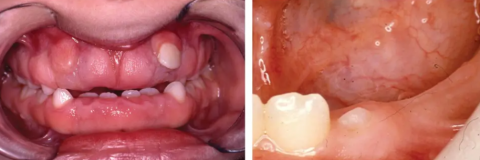

This intra-oral image shows a partially erupted posterior molar with surrounding inflamed gum tissue. The tooth is covered by soft tissue, creating a pocket that traps bacteria and debris. This presentation is consistent with a localized gum infection associated with a partially erupted or impacted tooth.

Partially erupted molar